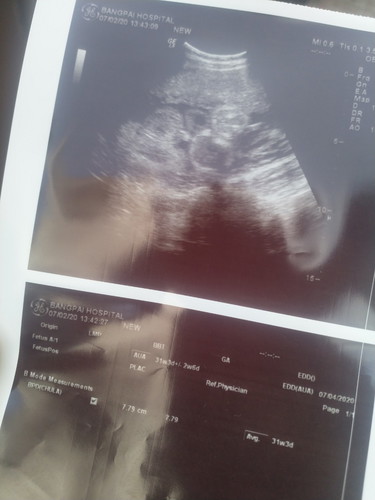

ช่วยดูทีคะ ตรงไหนจู๋น้อง ?

สอบถามคะ หมอบอกเป็นผู้ชาย แต่เราดูไม่เห็นแหลมๆเลย แม่ๆมองออกไหมคะ กลัวคลอดแล้วเป็นหญิง เพราะแม่จะได้กล้าเอฟชุดลูกคะ 5555

ภาพไม่ชัดเลยจ้า แต่ถ้าหมอฟันธงแล้ว แสดงว่าเห็นจู๋แล้ว ยังไงก็ไม่หดหายแล้วจ๊ะ